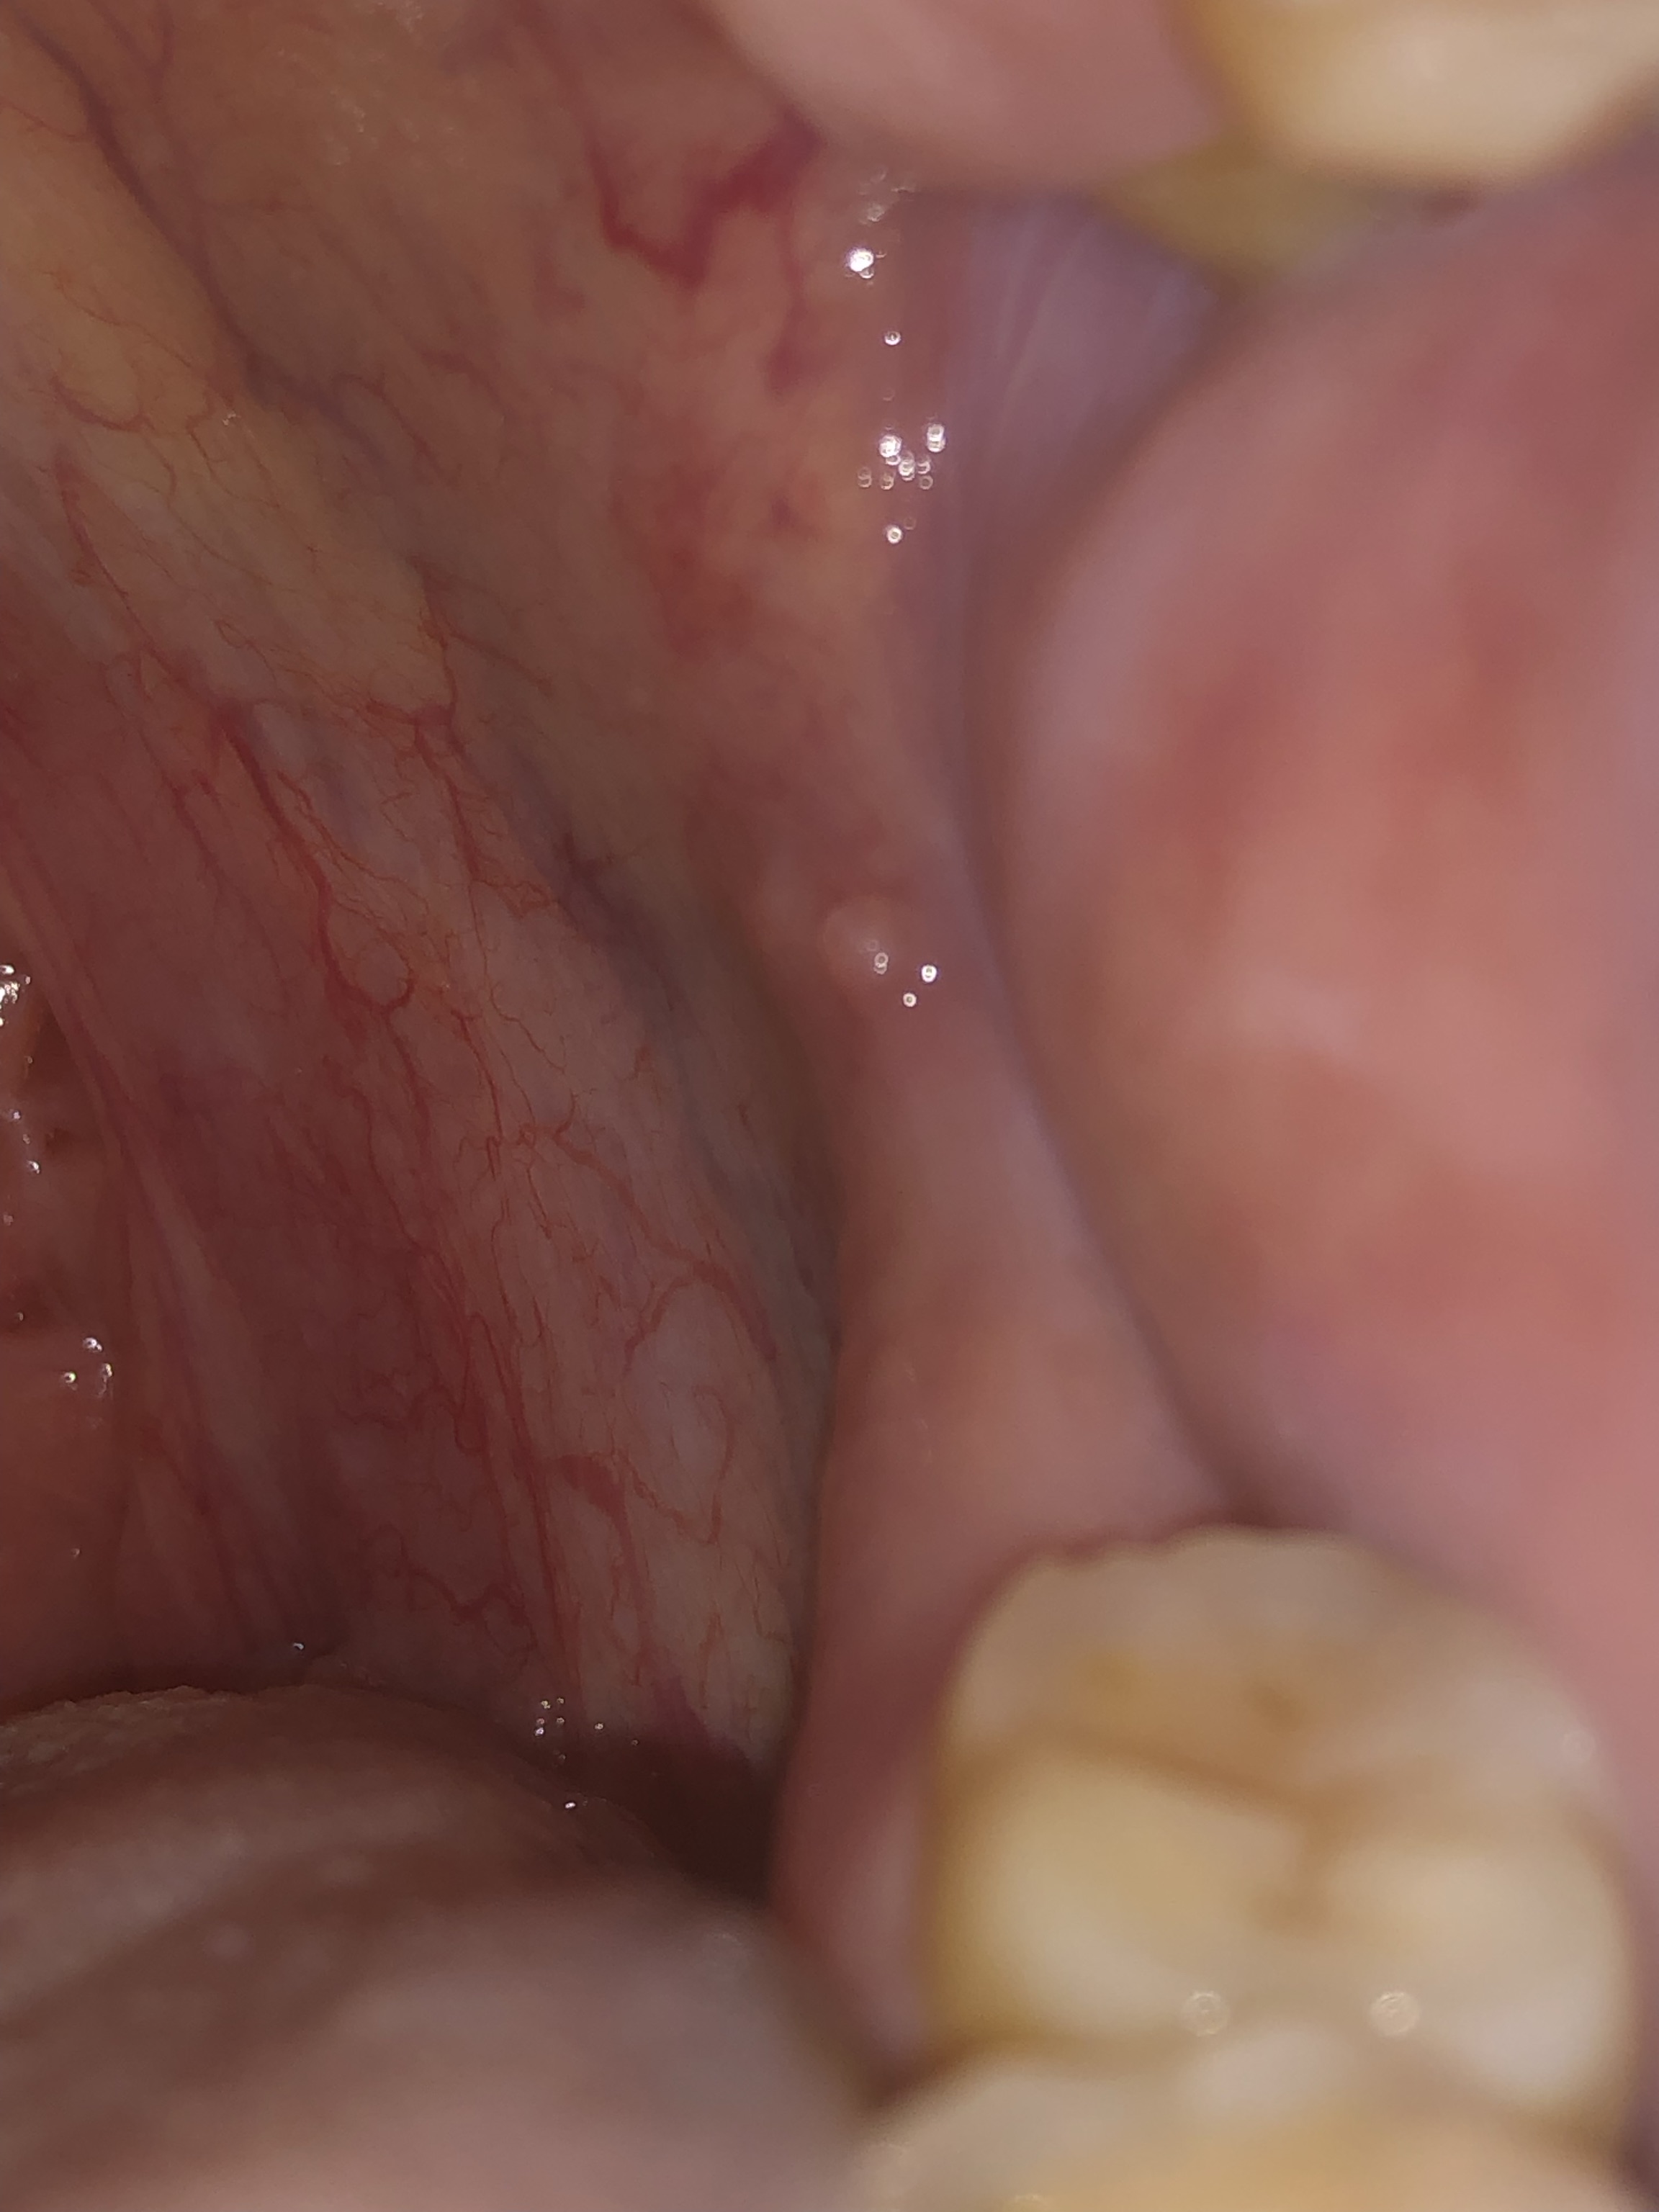

Dạ bác sĩ cho t hỏi miệng bị nổi hai mụn trong góc hàm trong miệng như hình t gửi là bị gì ạ.xin cám ơn bác sĩ